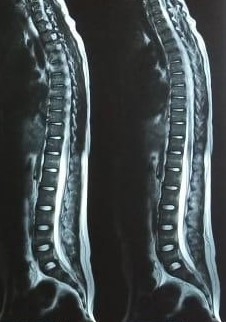

Such kind of unusual presentation involving more than one joint can occur in few conditions like disseminated infection, autoimmune diseases, cancer etc. Looking to the event of Chickenpox, I suspected deep seated infection. I advised MRI scan of right shoulder, spine and left gluteal region. His blood culture, the test to find out the species of invading organism, was ordered. I also sent investigations to rule out autoimmune disease. His MRI of left gluteal region suggested multiple collections of fluid within and surrounding muscles of hip joint. MRI of spine suggested swelling in lower vertebras and swelling of a joint in the pelvic bone (Secro-Iliac joint). His MRI of right shoulder also suggested similar collections and severe damage to one of the muscles of his shoulder joint. The fluid within the pockets was aspirated and sent for evaluation of the organisms involved but did not revealed any organism. His blood culture report sent two days before became available now. It suggested a very dangerous organism MRSA (methicillin Resistant Staphylococcus Aureus). This is a notorious organism that invades in to the blood through a breach in the skin. This boy had chickenpox. The blisters of the chickenpox eroded the skin and paved way for the organisms to enter his blood stream. In the blood the organisms escaped his immune system and multiplied, travelled and settled at regions of spine, left hip and right shoulder and created multiple abscesses. If effective treatment not initiated soon, his joints may get permanently damaged.

He responded well to the appropriate antibiotic treatment. Fever subsided after three days and pain in right shoulder disappeared completely. After a week of treatment was able to walk without pain. His appetite improved. Now he was able to perform his daily activities without support. He was discharged before two weeks with further instructions. He did well at home. He came for the follow up after two weeks. Repeat MRI showed significant improvement compared to previous scan.